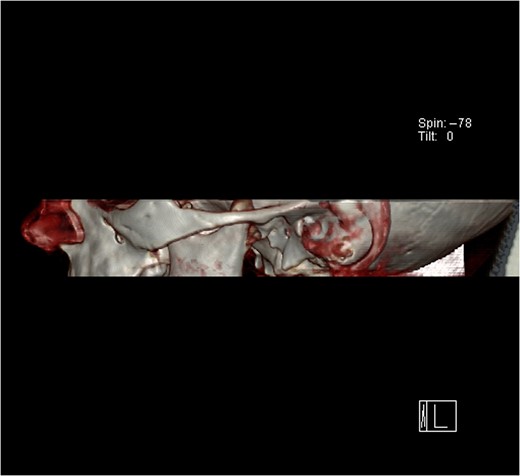

Computerized tomography (CT) image of the normal right temporomandibular joint.